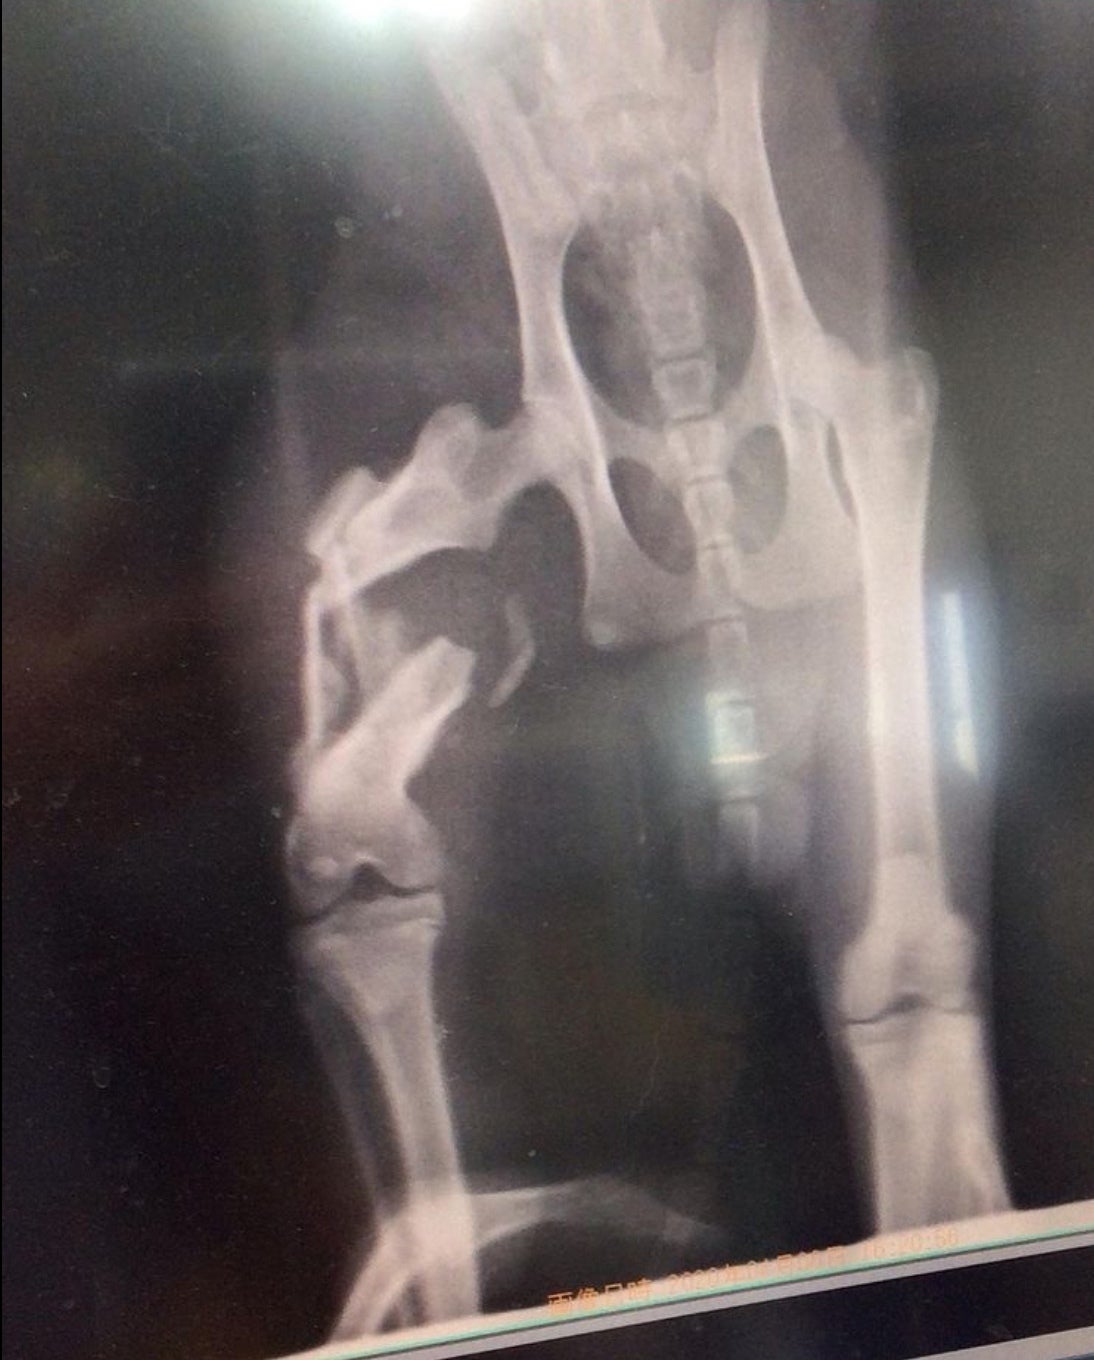

左手の骨折があり、親猫に捨てられたか、人によって捨てられたかは分かりませんが、

近所の方によると、一晩中鳴いていたそうです。

野生動物に襲われなくてよかった…本当に心細く、怖かっただろうなと思います。

我が家で初めて猫を飼うことになった子です。